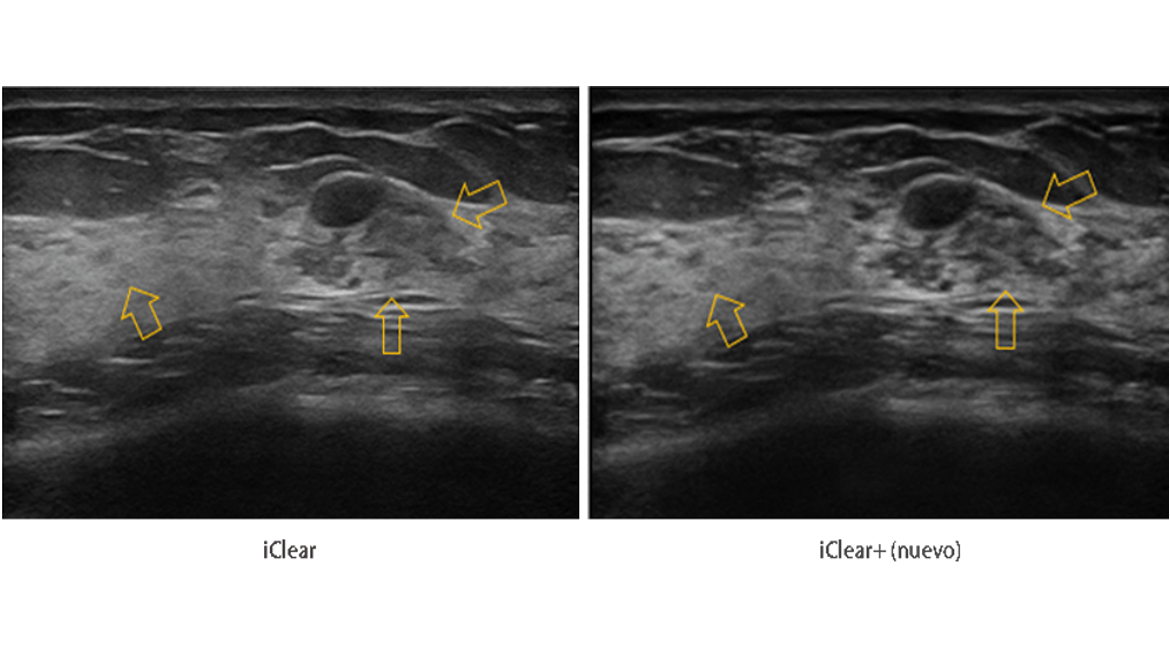

iClear+

Proporciona una mejor imagen con una sorprendente reducción de ruido y magnífica resolución de contraste para fácilmente identificar las lesiones, lo que mejora la confianza en el diagnóstico por ultrasonidos.